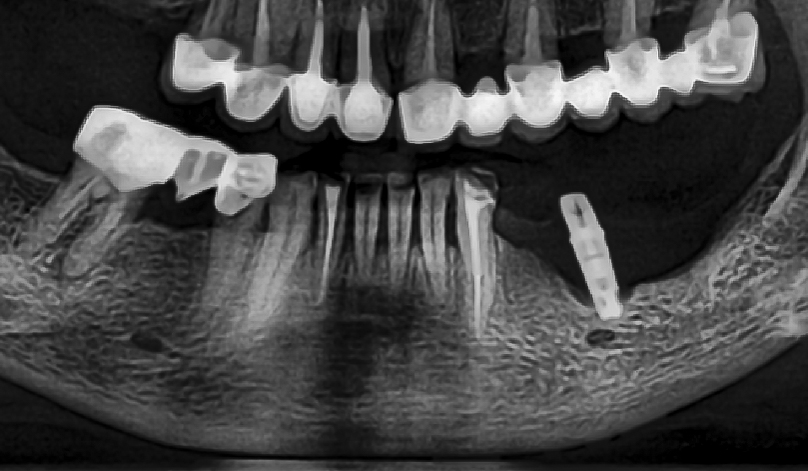

Acest proces poate dura cateva luni.[1] Cum putem verifica daca procesul de osteointegrare a implantului decurge asa cum ar trebui? Simplu, prin intermediul radiografiei dentare si masurare directa  ISQ  (Implant Stability Quotient)

Periimplantita este o afectiune inflamatorie care afecteaza tesuturile din jurul unui implant osteointegrat, ducand la pierderea osului de sustinere si la esecul implantului. Se poate dezvolta imediat dupa plasarea implantului sau chiar cativa ani mai tarziu si se manifesta prin sangerare, supuratie, mobilitatea implantului si pierderea osoasa radiografica.[5]